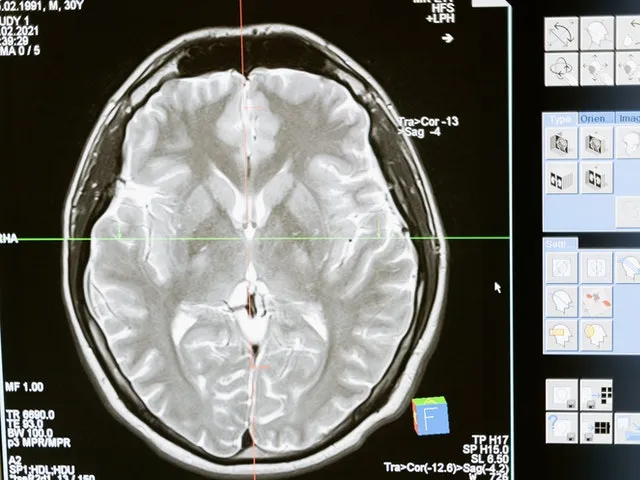

- Nie jest to "wada charakteru" czy "brak silnej woli", lecz choroba mózgu, zmieniająca jego chemię i funkcjonowanie.

Mózg w pułapce: Jak alkohol chemicznie zmienia sposób myślenia i odczuwania

Chroniczne spożywanie alkoholu prowadzi do głębokich zmian w chemii mózgu. Alkohol wpływa na neuroprzekaźniki, takie jak dopamina i serotonina, które odpowiadają za nastrój, motywację i odczuwanie przyjemności. Z czasem mózg adaptuje się do obecności alkoholu, co prowadzi do rozwoju tolerancji i fizycznego uzależnienia. Te zmiany chemiczne bezpośrednio wpływają na sposób, w jaki osoba uzależniona myśli, odczuwa i zachowuje się, tworząc błędne koło przymusu picia.Psychiczne objawy towarzyszące uzależnieniu od alkoholu

Chroniczne picie alkoholu nie tylko wpływa na stan psychiczny, ale także prowadzi do trwałych uszkodzeń mózgu, które znacząco obniżają jakość życia i codzienne funkcjonowanie.